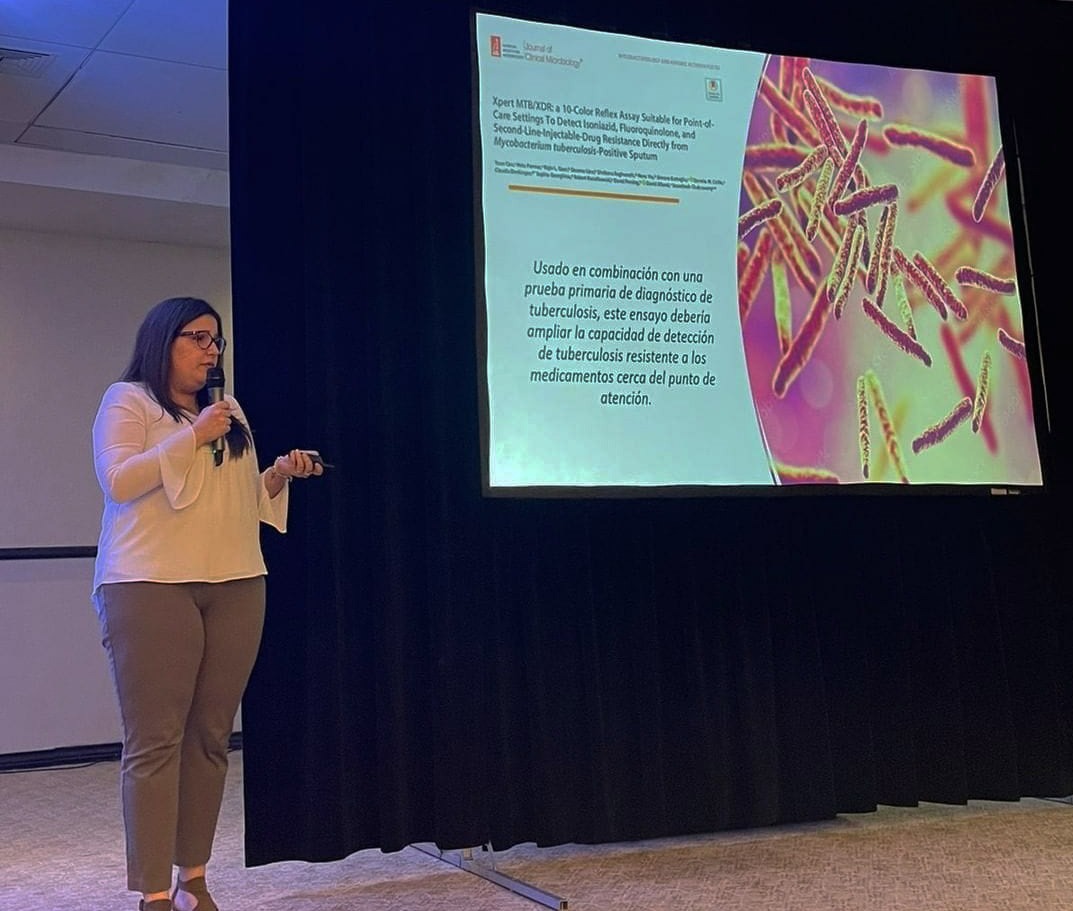

Microbióloga: detección temprana de tuberculosis resistente a fármacos evita complicaciones

La supervisora general del departamento de microbiología de Referencia Laboratorio Clínico, Joana Bacalhau, indicó que el diagnóstico temprano de la tuberculosis (TB) y el inicio rápido del tratamient…